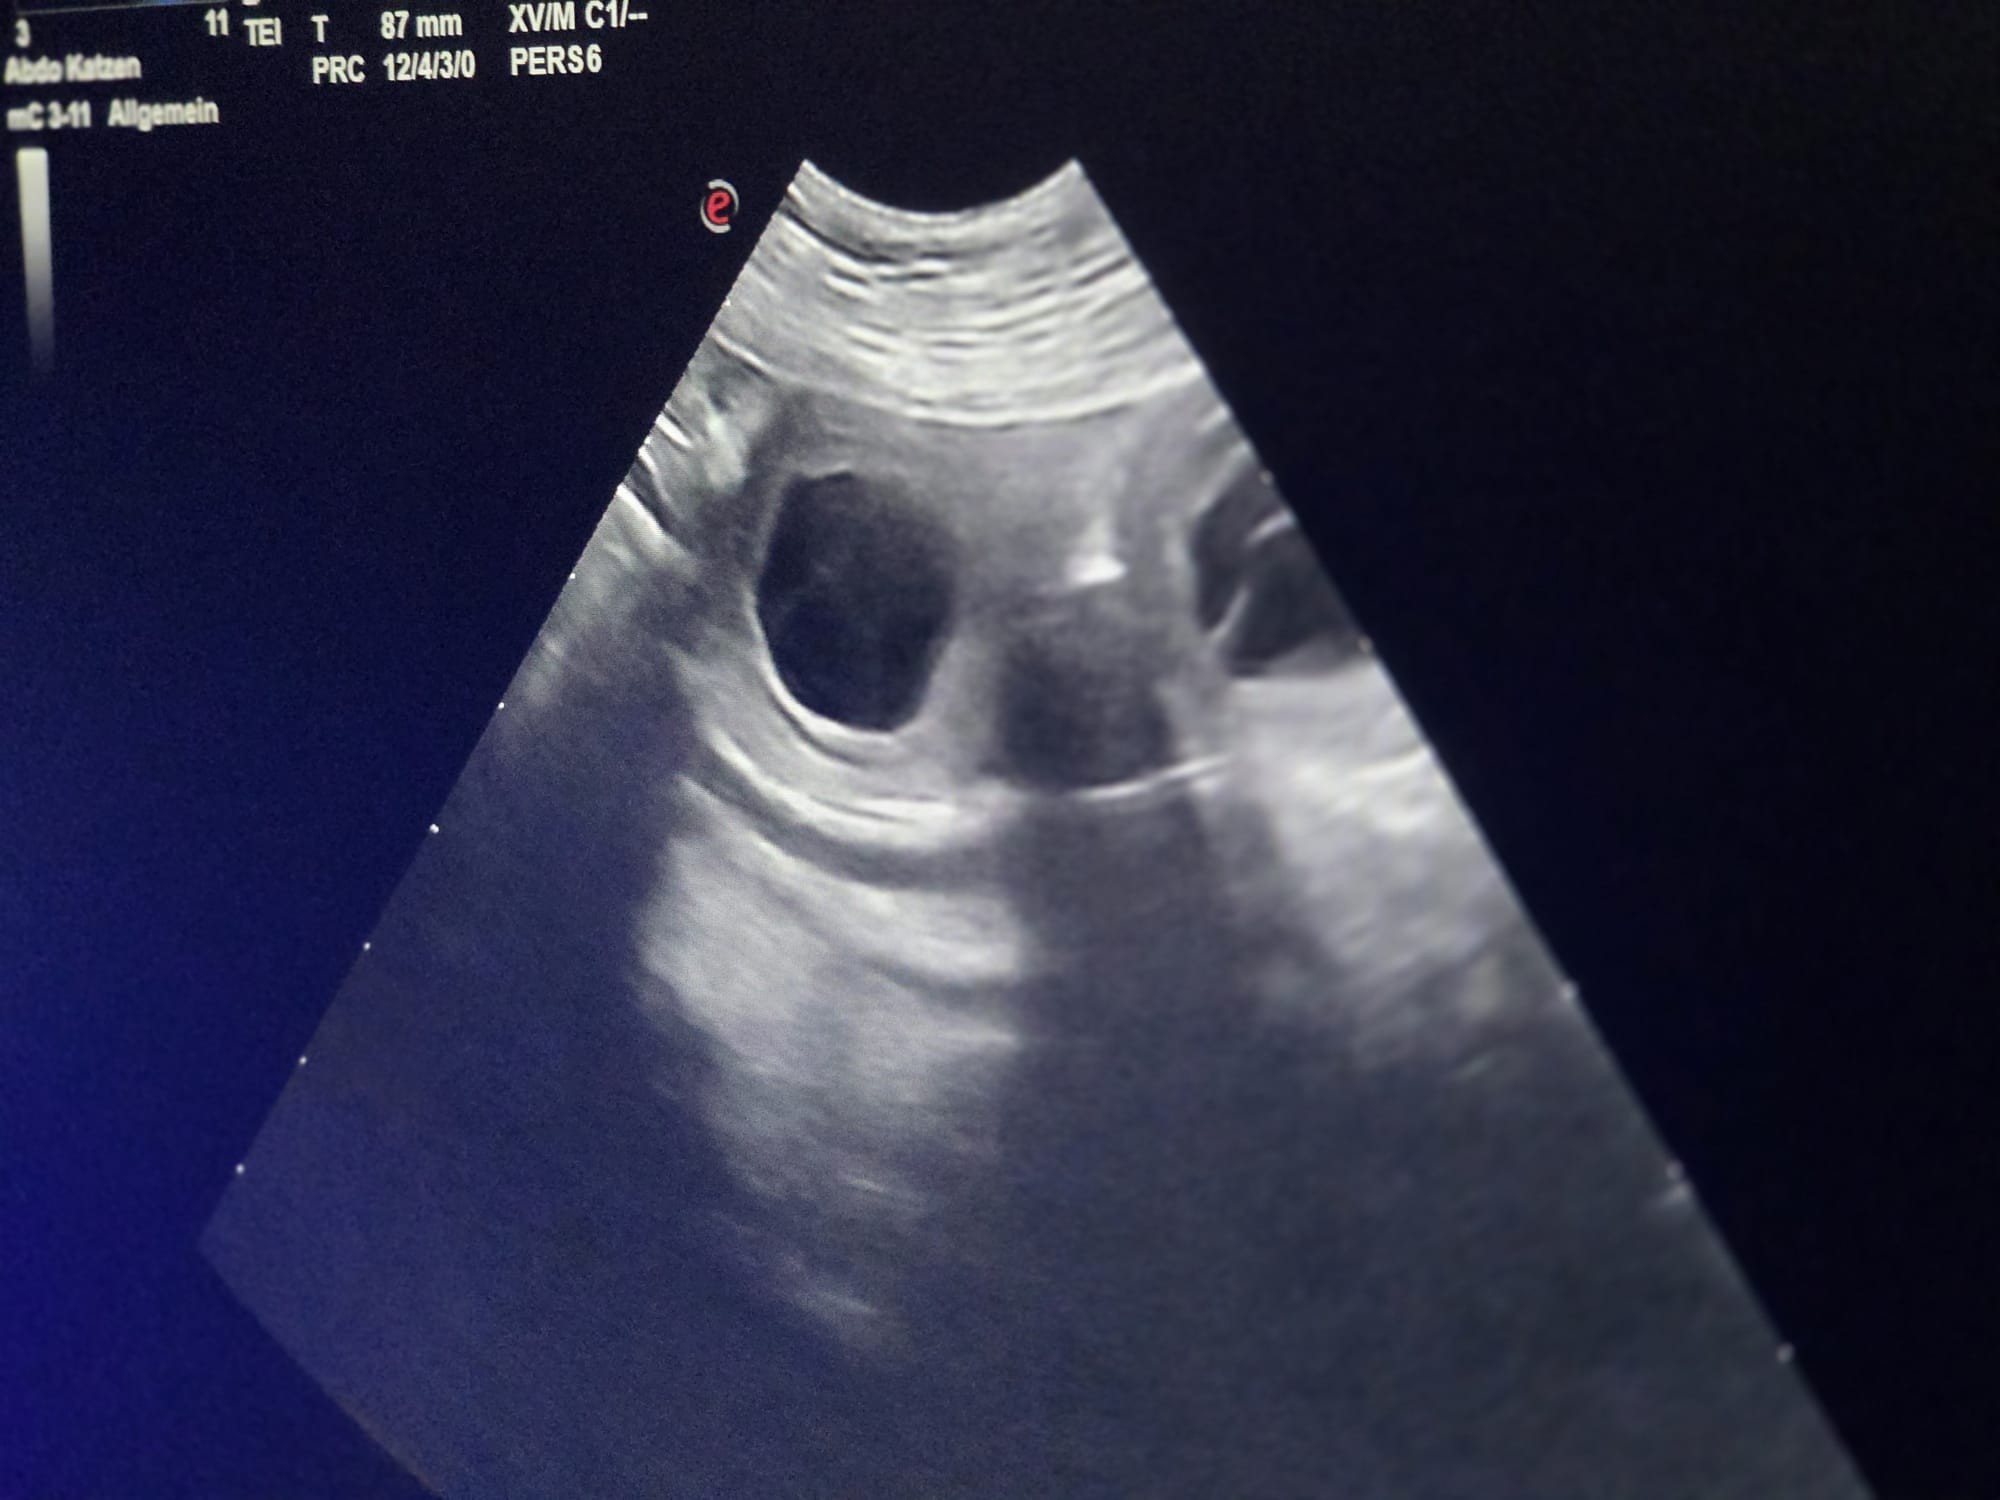

Am

13.3.2026 war es endlich so weit - der langersehnte Ultraschalltermin.

Und Freitag der 13. hat uns Glück gebracht! Wir konnten mehrere

Fruchtanlagen sehen und freuen uns sehr!